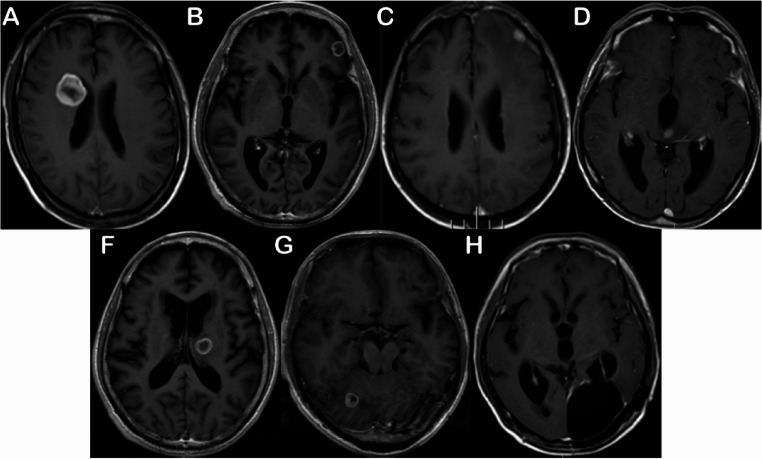

Methods: The final analysis included 112 pathologically definite NSCLC patients with BM, treated at Sanjiu Brain Hospital between July 2014 and December 2020, who had not undergone whole brain radiation therapy before LM diagnosis. LM diagnosis was made if the patient had a history of pathologically confirmed lung cancer, new signs and symptoms of the nervous system, and positive CSF cytology or typical MRI findings. The data were retrospectively collected following the initial BM diagnosis until the patient was diagnosed with LM or died of any cause without developing LM. MR images were reviewed independently by two well-experienced radiologists in a double-blind manner. The primary outcome was to identify factors associated with the development of LM following BM diagnosis.

Results: In the present study, two study cohorts were analyzed: (1) NSCLC-BM patients who subsequently developed LM (n = 56), and (2) NSCLC-BM patients who did not develop LM until death (n = 56). The median follow-up time for the entire cohort was 9.9 months (IQR, 4.2-18.2 months) following BM diagnosis. Univariate analysis identified several potential risk factors including EGFR/ALK/ROS1 mutations (OR = 3.868, 95% CI 1.583-10.079, P = 0.003), ventricle- or pia mater-adherent BMs (OR = 10.278, 95% CI 4.203-27.375, P < 0.001), and stereotactic radiosurgery (SRS) as a protective factor (OR = 0.024, 95% CI 0.001-0.12, P < 0.001). Multivariable logistic regression confirmed adherent BMs (OR = 9.846, 95% CI 2.981-40.176, P < 0.001) and driver mutations (OR = 5.501, 95% CI 1.444-25.893, P = 0.018) were independent predictors of increased LM risk, while SRS significantly reduced LM risk (OR = 0.029, 95% CI 0.001-0.179, P = 0.002). Fine-Gray competing risks analysis (death without developing LM as competing event) yielded consistent results: adherent BMs (HR = 3.17, 95% CI 1.68-5.97, P < 0.001), mutations (HR = 2.99, 95% CI 1.03-8.70, P = 0.045), and protective effect of SRS (HR = 0.25, 95% CI 0.14-0.46, P < 0.001). A nomogram incorporating these three factors demonstrated excellent predictive performance with an area under the receiver operating characteristic curve of 0.885 and a C-index of 0.805.